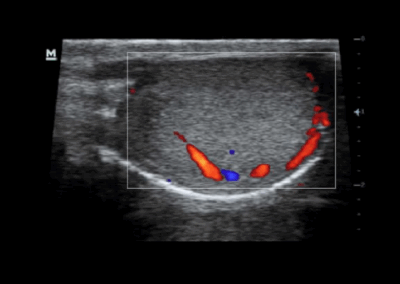

Z60

Sistema de diagnóstico ecográfico.

El sistema Z60 es una buena opción para aquellos que requieren un rendimiento de imagen de alta calidad, una movilidad simple y asequibilidad cuando se trata de imágenes ecográficas avanzadas. Con configuraciones completas y un diseño integrado, el Z60 es el resultado de los esfuerzos continuos y decididos de Mindray para hacer que la atención médica primaria sea más eficiente, eficaz y accesible para todos.